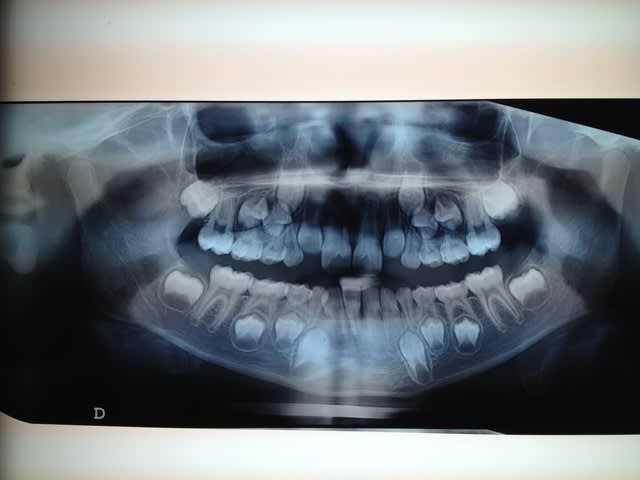

Bonjour! Enfant de pas encore 7ans présentant une DDM.L'ortho me demande d'extraire 53,63,73,83 (c'est la mode dans mon coin!)car manque de place pour la venue de la 12 et 22.Je trouve cela particulièrement traumatisant pour une petite fille de cette age.Ne peut-on pas selon vous passer par d'autres solutions en commençant par exemple à reserrer 11 et 21.

Ci joint la pano et merci pour vos réponses

Quelle solution pourrait-on bien proposer avec seulement une panoramique comme ça ?

Le pic de croissance est encore loin.

7 ans est trop tôt pour un pilotage des canines qui se mettent en place vers 11/12 ans

Effectivement l’extraction des canines lactéales va permettre aux latérales de venir sur l’arcade, mais après ?

C’est repousser le Pb. en plus grave car les dents de lait sont des mainteneurs d’espace. Si on enlève les canines lactéales, on perdra encore plus d’espace, ce qui n’est pas le but.